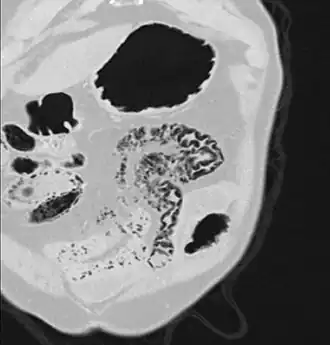

Pneumatosis intestinalis in the coronal computed tomography in lung window. It can be seen next to gas entrapment in the bowel wall and gas in the stomach wall and in numerous vessels, including the portal vein into the liver. -

Pneumatosis intestinalis in computed tomography with intestinal ischemia. Lung window for better representation of the gas deposits in the intestinal walls. -